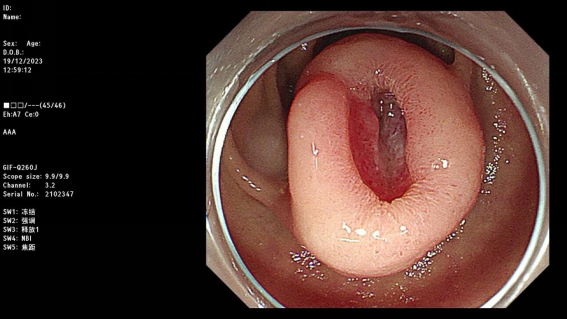

2023年12月19日,手术进行。由于包块距离十二指肠乳头仅约1cm,且包块周围血管异常丰富,在刚刚开始手术的时候就出现了出血情况,团队及时止血并进行仔细分离。

全层剥离十二指肠腔部分的包块后,内镜进入到腹腔继续分离腹腔部分的包块。手术视野血管增多,增大了在腹腔内分离包块的手术操作难度。外科出身的胡兵教授凭借对解剖结构的熟悉以及丰富经验,经过4个多小时的不懈努力,将包块完整地切除下来。

然而,创面缝合又是一大难关。病变是通过全层剥离方式切除,故创面较大较深,且十二指肠管腔结构原因导致操作空间狭小。胡兵教授采用双荷包缝合技术耗时半小时对创面进行了缝合。